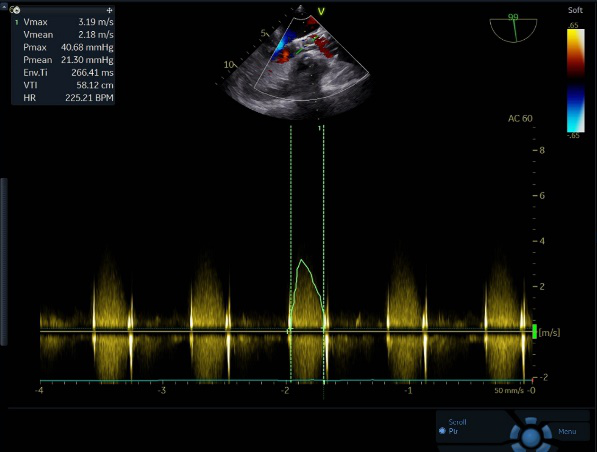

手术即刻超声测量,主动脉瓣工作良好,无反流,与术前超声测量数据对比,流速、跨瓣压差得到有效改善。

超声评估

术前、术后血流动力学评估